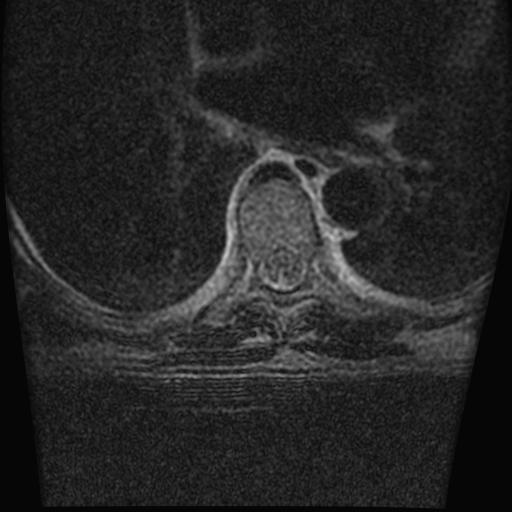

68岁男性,胸部疼痛,不适。

胸7椎体楔状变形及信号异常,附件未见明显异常信号.椎间隙正常.未见软组织块影.考虑骨质疏松所致压缩性骨折可能大.

胸7椎体楔状变形及信号异常[t1t2 均为低信号],附件未见明显异常信号.椎间隙正常.未见软组织块影.考虑陈旧性压缩性骨折伴退变。

首先需除外单发成骨性转移瘤可能。

转移瘤也不能排除